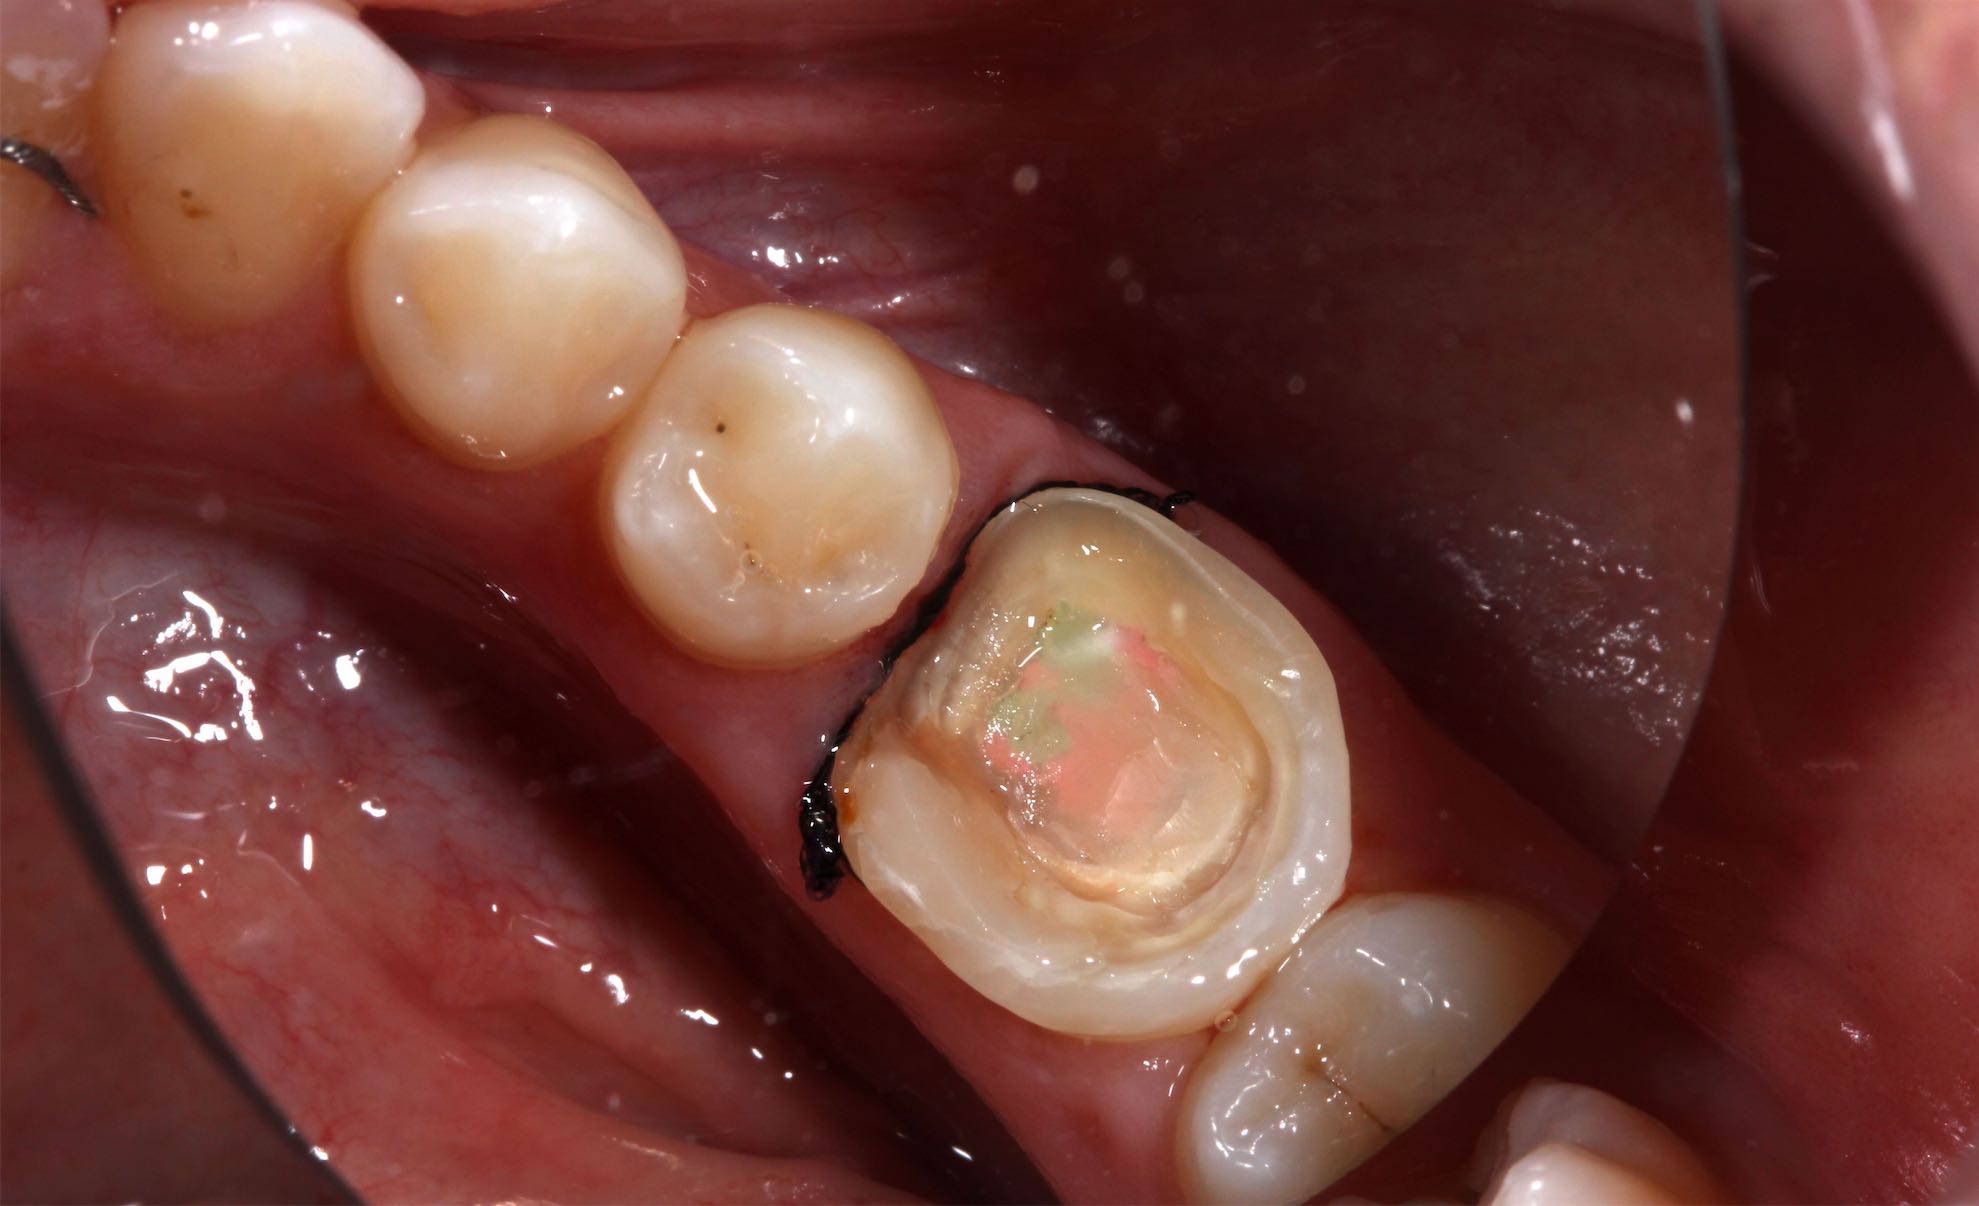

Odontología Restauradora Incrustaciones CAD-Cam

BeforeAfter